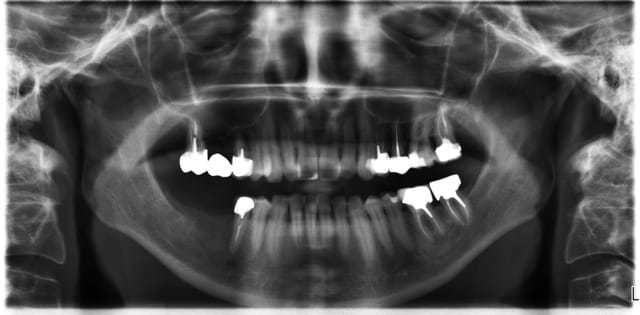

Si je comprends bien on ne peut poser tes implants si on a les dents en place au préalable ...En postérieur c'est léger , les dents étaient absentes lorsque tu as vu ce patient ?

Ned2 tfirxz - Eugenol

De l'intérêt de garder une dent en secteur 2 ?

Il y a des proximités pour le moins surprenantes .

Des absences d'implants dans certaines zones également .

J'en reviens au premièrement , tu ne mets des implants qu'après extraction , donc on t'enverra des patients avec les dents ...

Maintenant concernant la demande de scans : je poste ce cas, une patiente vient me voir avec son scan car elle a consulté d'autres "spécialistes" et on lui refuse la pose d'implant secteur 4 où alors avec greffe préalable..Ca se discute..pas de temps à perdre je sais faire autrement..

Avec la chir trans gingivale technique MIMI ( Oui..un post sur la technique bientôt ..) j'ai pu placer deux 3,5/8mm..aurai je eu le meme résultat avec un lambeau..j'en doute..Les couronnes sont en titane. Recul clinique 2 ans ras. Simple efficace rapide moins onéreux satisfaisant pour le praticien et la patiente..